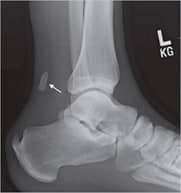

X-rays provide clear images of bones. They can show bone spurs on the back of the heel, which may be present in patients with insertional Achilles tendinitis. In cases of severe noninsertional Achilles tendinitis, X-rays may show calcification in the middle portion of the tendon.

Calcification within Achilles tendinitis

This X-ray shows calcification within the Achilles tendon in severe noninsertional Achilles tendinitis.